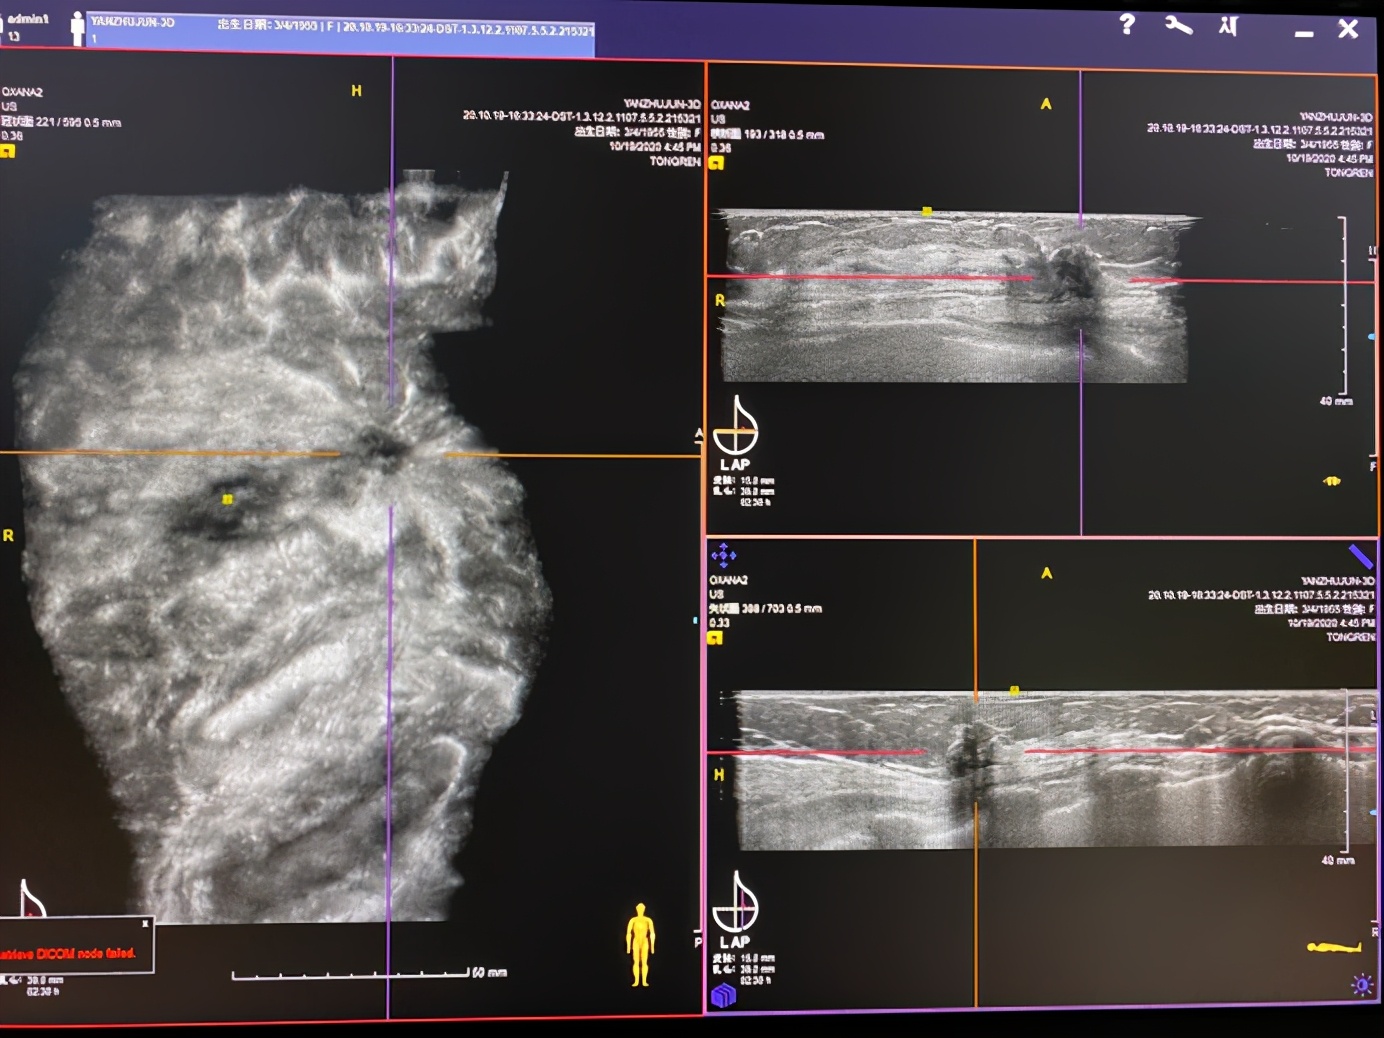

4. 提供更为直观的诊断信息,可读片性强。ABVS 冠状面重建对于显示乳腺恶性病灶较二维超声显示信息更加丰富,为诊断鉴别乳腺癌提供更为直观的影像学证据。

(三合一视图:大型冠状图显示浸润性导管癌典型「太阳花」征和毛刺征)